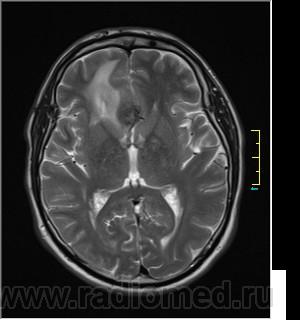

Ax T2:

частично функционирующая аневризма

Иначе говоря, аневризма с хронической геморрагией, т.к. мы видим фракции крови различного возраста.

По-моему, аневризма с пристеночными тромбами.

Постепенное пристеночное образование тромбов приводит к появлению типичного для аневризмы феномена -слоистости МР сигнала в полости аневризмы. Данная картина демонстрирует слоистый характер тромботических масс в полости аневризмы .Функционрирующая часть имеет низкий сигнал во всех режимах сканирования. Дополнительно-перифокальный отек.

А может более корректно интерпретировать как частично тромбированная аневризма... Уж коь речь идет о фракциях, ну то есть о тромбе по сути.... Ну и плюс перфокальный отек головного мозга (вероятнее цитотоксический+вазогенный).